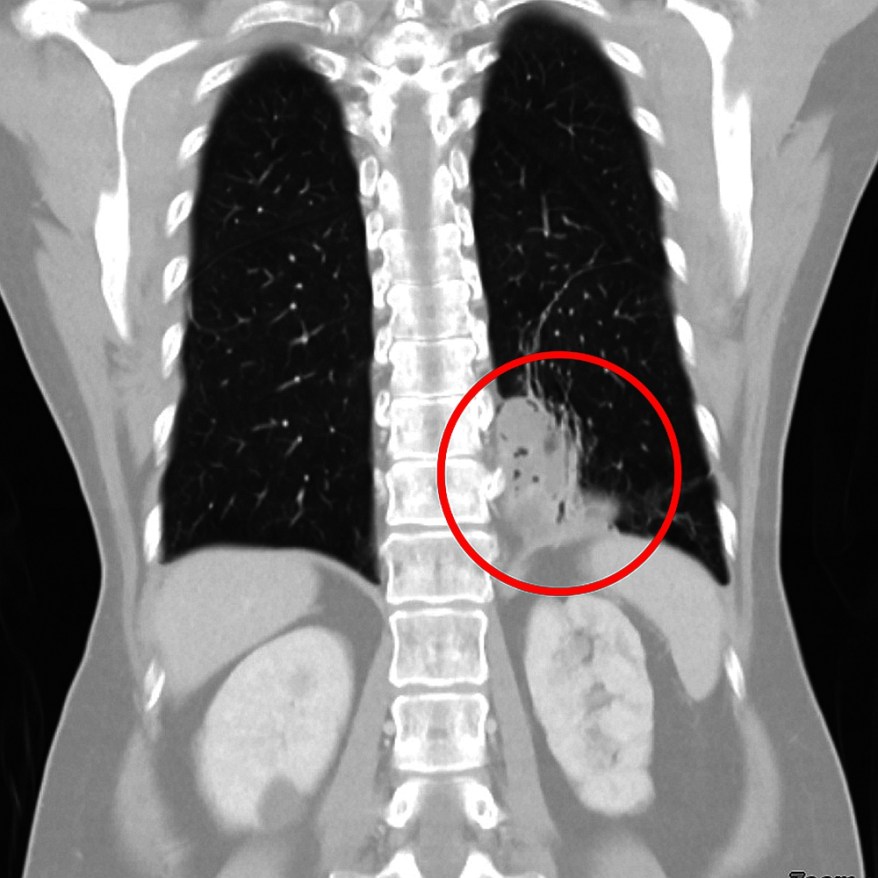

病情未見好轉,讓黃女士感覺不對勁,轉而到臺中慈濟醫院胸腔外科詢問第二意見。主治醫師柯志霖推斷黑影疑似腫瘤或肺膿瘍,為求謹慎,安排電腦斷層動脈血管攝影,驚見病人左下肺與橫膈膜中間,存在一條異常血管,確認「這並非單純支氣管擴張症,而是罕見的『游離肺』」。

柯志霖醫師指出,黃女士的游離肺個案之所以是「極為罕見」。因為大多數游離肺病人致病的血管是從胸主動脈過來,而黃女士致病機轉則是因胃的左胃動脈跑上來到肺臟形成游離肺。

「一般人胸主動脈進入腹腔後會分支為左胃動脈,但黃女士的左胃動脈卻又出現異常分支,並在腹腔繞了一個髮夾彎,經橫膈膜鑽回胸腔進入肺臟,多出來的血管使肺部出現多種症狀。」柯醫師採單孔式胸腔內視鏡微創手術,替黃女士切除左下肺葉,縫合左胃動脈血管,處理胸腔多處沾黏,手術歷經四小時完成,手術傷口直徑約4公分,出血少、恢復快,切除病灶後不再有咳血症狀。